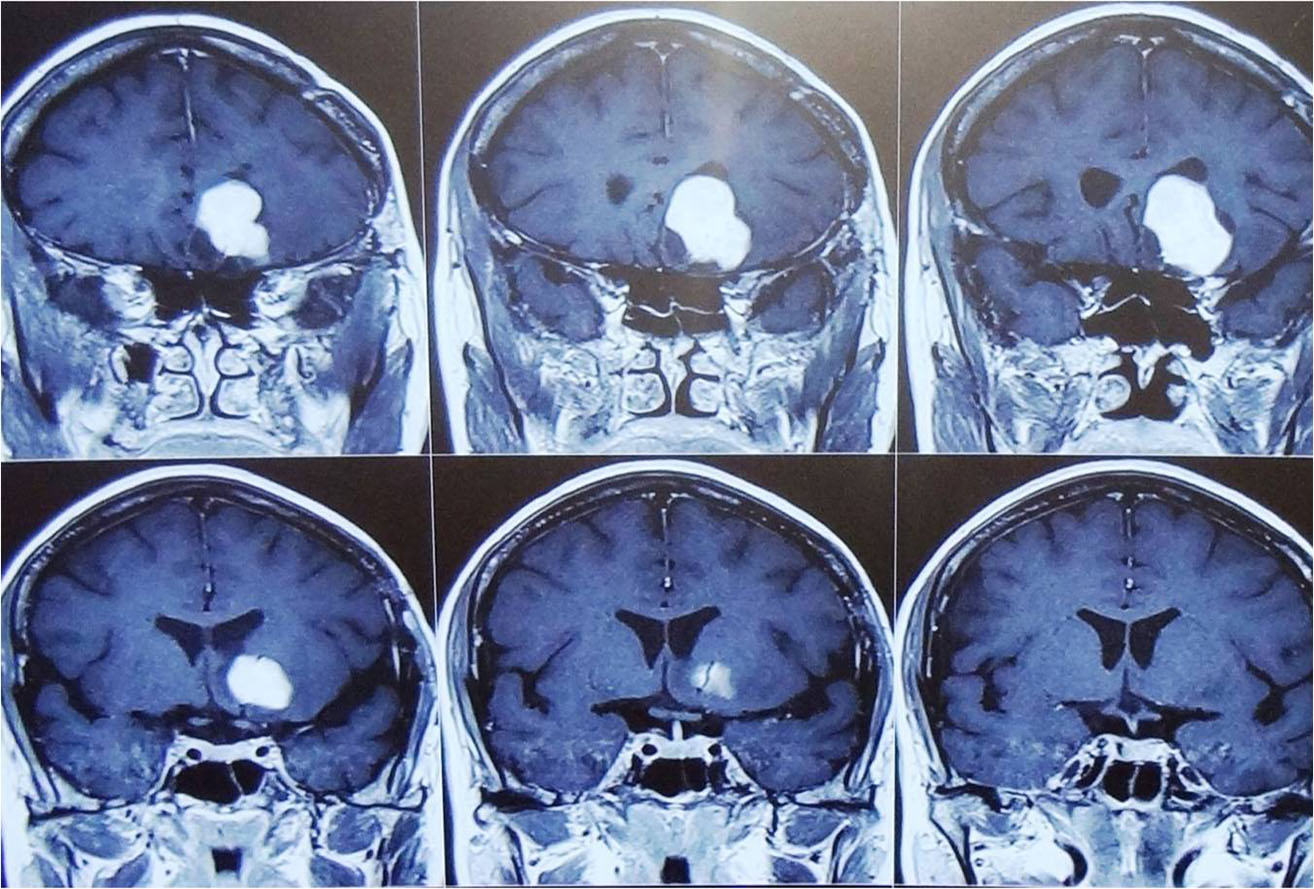

Traumatic Brain injury is defined as damage to the brain resulting from external mechanical force,

commonest causes of brain injury are vehicular accidents, assaults, and accidental falls etc.

Traumatic Brain injury is a major cause of death and disability worldwide, especially in children and young adults.

Brain injuries can be minor or major life threatening. The signs and symptoms depend on the severity of injury.

Minor injuries are usually treated with medications and constant monitoring. Moderate to severe injuries require treatment in neurosurgical ICU and may require emergency surgery.